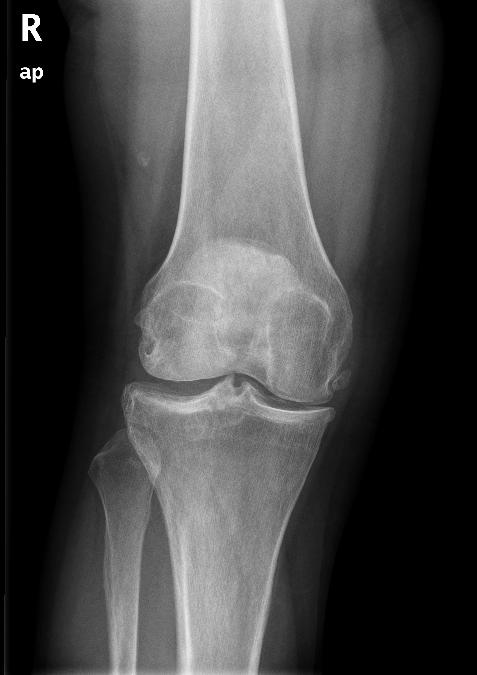

术前正位片

患者女性,52岁,因右膝关节疼痛2月为主诉入院。入院根据病史、查体和X线片诊断为右膝骨关节炎,经常规入院检查,未发现手术禁忌症,在硬膜外麻醉下行关节镜清理手术。术中应用止血带止血,手术过程顺利,手术时间为35分钟。术后给予弹力绷带包扎右下肢,术后第一天即嘱病人下地活动,疼痛较术前明显好转。术后给予了抗生素等药物,但未应用抗凝药物。术后第三天,患者出现右下肢肿胀、胸痛、呼吸困难,经行下肢超声和肺CT检查,结合血气分析等指标,呼吸科诊断为右下肢深静脉血栓形成,肺栓塞,转入呼吸科治疗。经溶栓、抗凝、支持等治疗2周后,病情痊愈出院。出院后继续服用华法林,定期检查凝血功能,维持INR值在1.5-1.5。